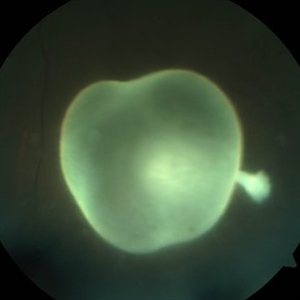

A 35-year-old healthy male presented with complaints of floaters in his left eye since 2 weeks. On examination, visual acuity was 6/6, posterior pole was normal, the inferior fundus showed a live intravitreal cysticercus with a scolex, that was photophobic.

Photographer: Kiran Sharma, Guru Nanak Eye Centre, Maulana Azad Medical College, New Delhi, India

Imaging device: Zeiss Visucam

Condition/keywords: cysticercosis, intravitreal, scolex